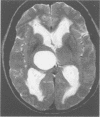

Images in this article